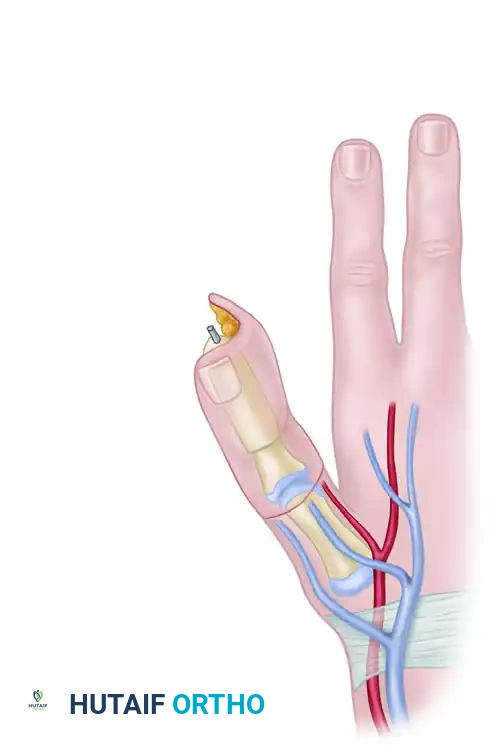

Bone Graft Harvest and Fixation

A corticocancellous bone graft is harvested from the ipsilateral iliac crest. It must be meticulously sculpted to match the approximate length and thickness of the normal contralateral thumb.

* Sizing: The tip of the reconstructed thumb, when adducted, should reach within approximately 1 cm of the index finger proximal interphalangeal (PIP) joint.

- Excise any scar tissue from the thumb bone stump and freshen the bone end to bleeding cortical bone.

- Create a recess (step-cut or peg-in-hole) in the base of the proximal phalanx or the thumb metacarpal.

- Insert the sculpted iliac crest bone graft into the recess.

Fix the bone graft rigidly using crossed Kirschner wires (K-wires), intraosseous wiring, or small fragment plates and screws.

Biomechanical Alignment: For amputations at or proximal to the MCP joint, the iliac bone block must be fixed in approximately 30 degrees of flexion and 45 degrees of internal pronation. This precise positioning is critical to allow functional opposition of the reconstructed thumb to the fingers.

With the bone graft rigidly fixed, the harvested wraparound flap is brought to the recipient site.

- Wrapping the Flap: Wrap the soft tissue flap around the iliac bone graft. Ensure the lateral side of the flap is applied to the ulnar side of the bone graft. Trim the bone graft slightly if the soft tissue envelope is too tight; tension on the skin closure will compromise microvascular perfusion.

- Positioning: Loosely suture the flap in place, ensuring the nail is oriented dorsally and the neurovascular pedicle sits comfortably in the first web space without kinking or tension.

- Neural Coaptation: Using an operating microscope, suture the ulnar digital nerve of the thumb to the lateral plantar digital nerve of the flap using 9-0 or 10-0 nylon epineurial sutures. Suture the deep peroneal nerve of the flap to the superficial radial nerve branch on the dorsum.

- Arterial Anastomosis: Perform an end-to-end anastomosis between the princeps pollicis artery and the first dorsal metatarsal artery of the flap. If the princeps pollicis is inadequate, the radial artery at the wrist may be used via an end-to-side anastomosis.

- Venous Anastomosis: Establish arterial flow first to identify the most robust venous outflow. Suture the dorsal digital veins/saphenous tributaries of the flap to the cephalic venous system of the hand.

- Closure: Place small silicone drains beneath the flap if necessary, strictly avoiding proximity to the microvascular anastomoses. Close the skin loosely.